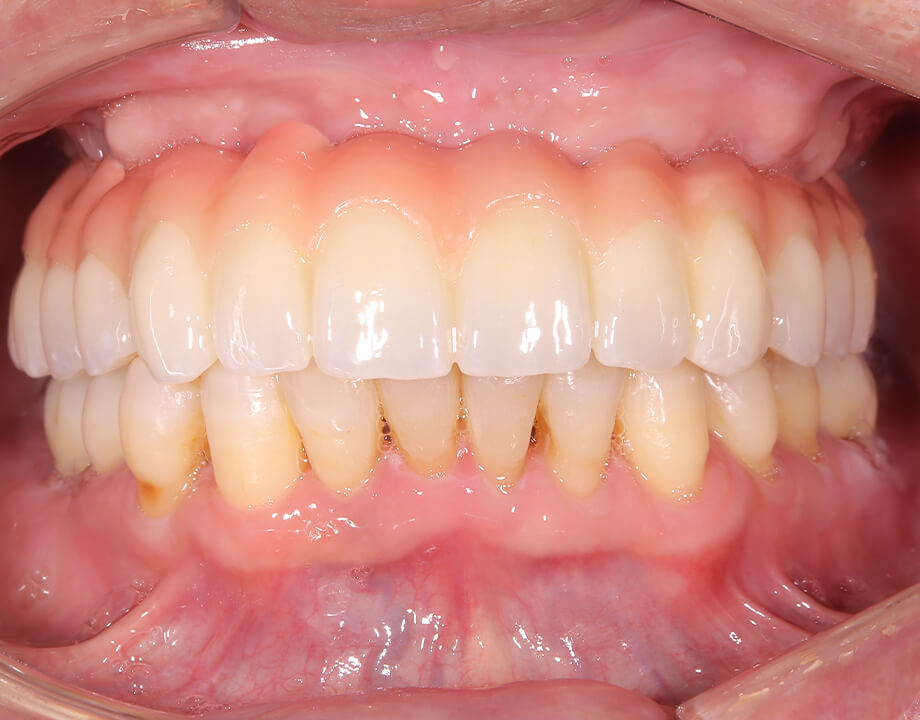

Case 01天然歯

ジルコニアレイアリング